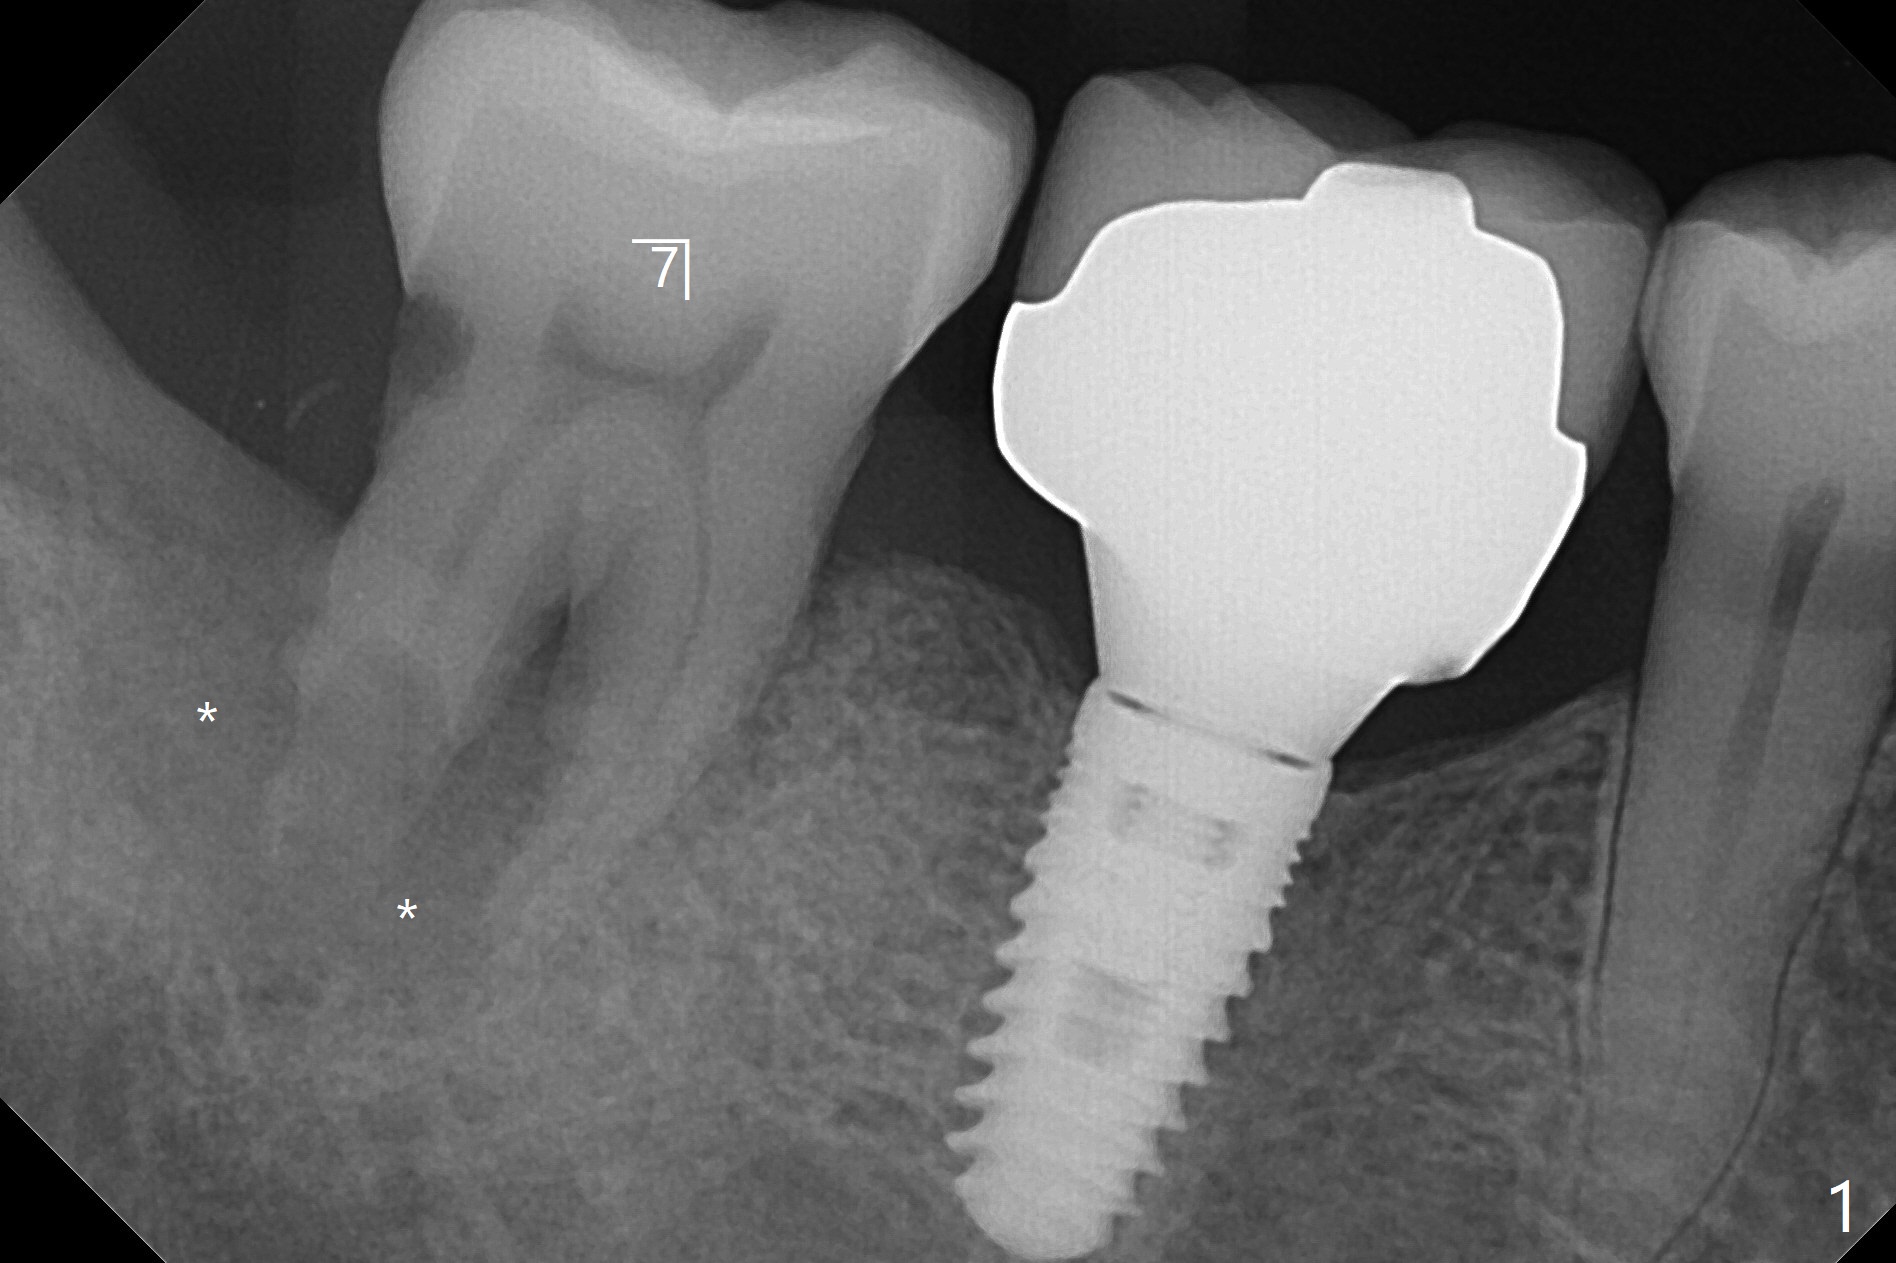

56岁男严重牙周炎,要求拔除右下7(图一),病人特别提出彻底清除炎性组织,GEM21S与皮质骨粉调袢5分钟后放置清创的牙槽窝(图二:*),覆盖Cytoplast,4-0 PTFE缝合。术后一个月膜游离(图三),撤线(缝线不是故意穿过膜)后,膜去除,下面骨粉好像稳定(图四至六)。